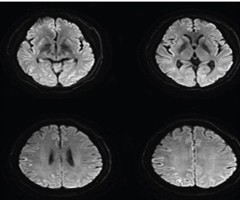

小脑性共济失调首发的克-雅脑病1例

摘要克-雅脑病(CJD)首发症状不典型,给早期诊断及鉴别带来了较大难度。步态1例以头晕、行走不稳的小脑性共济失调症状起病的散发型CJD。...